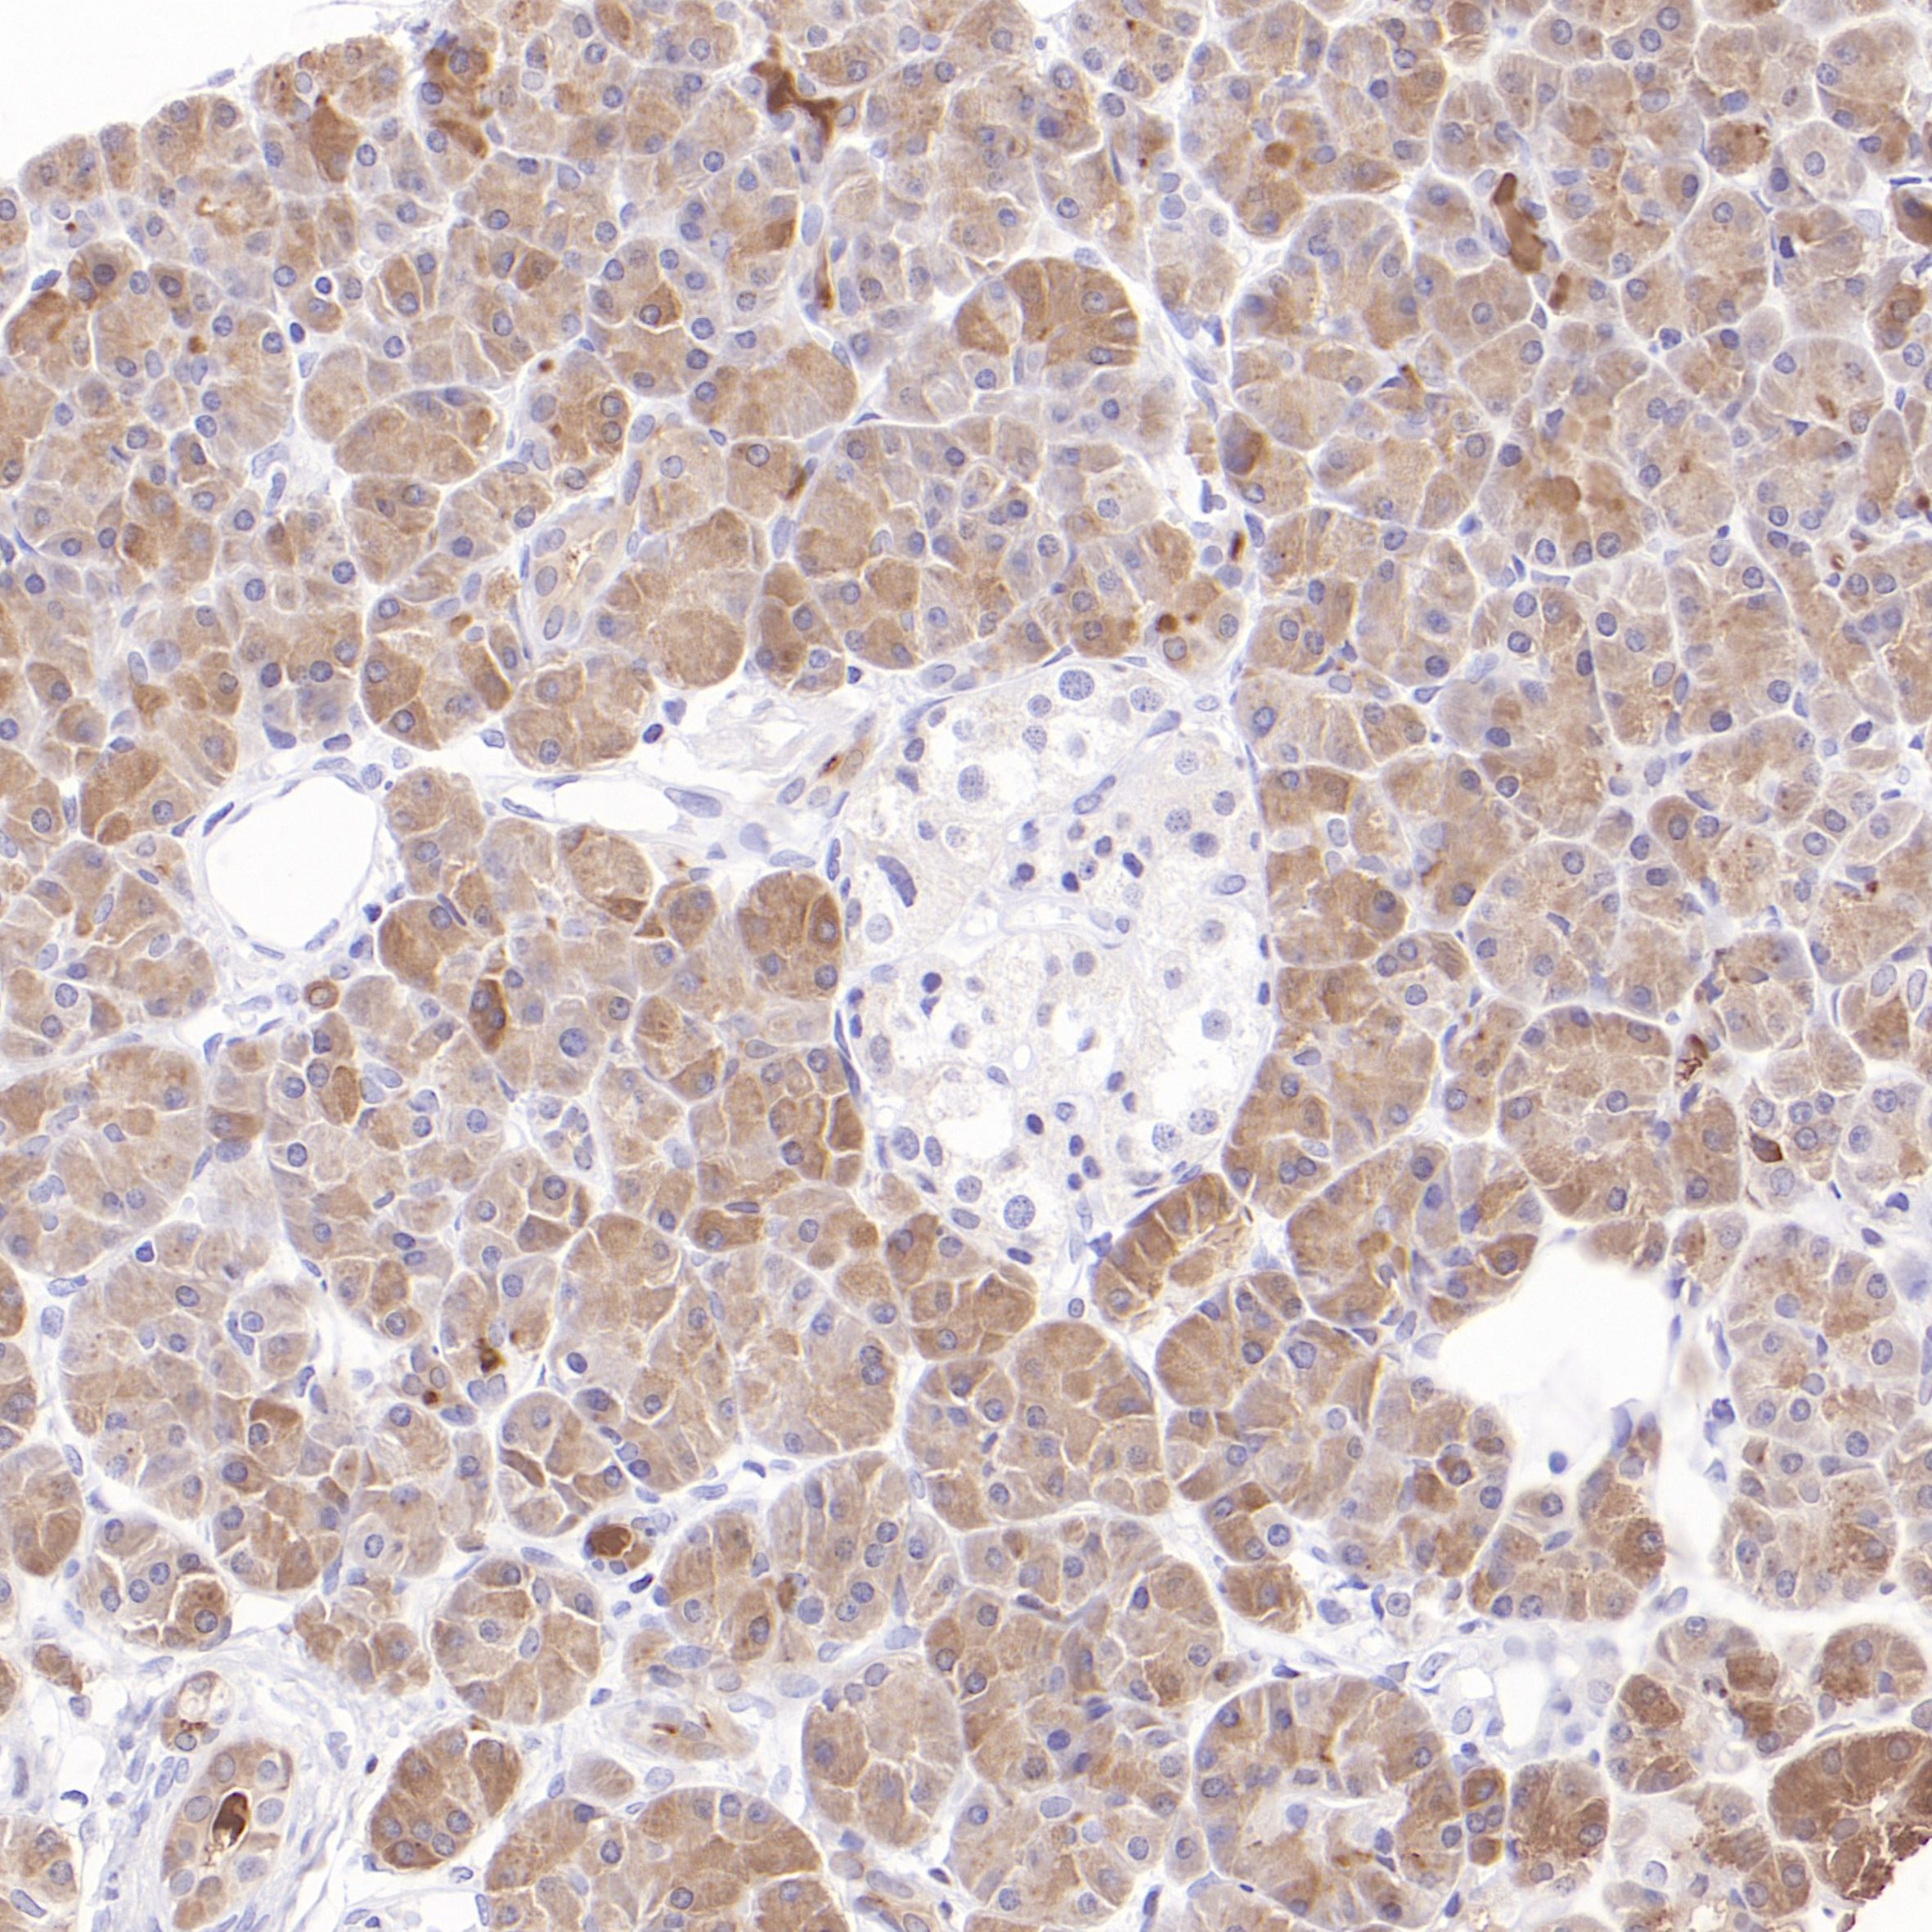

"PRSS1编码人类胰腺分泌的最主要的消化酶前体—人阳离子胰蛋白酶原,在十二指肠中被激活后会切割赖氨酸和精氨酸残基之后的膳食蛋白质。PRSS1在正常胰腺腺泡细胞中特异性富集,在胰腺导管腺癌中与癌旁组织相比反而较低或缺失。

在组织中检测PRSS1可作为急性胰腺损伤的生物标志物,且受损腺泡细胞中的PRSS1泄漏与疾病的严重程度存在关联。

胰腺